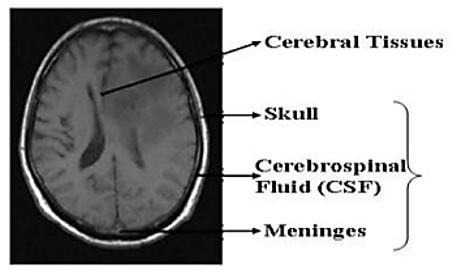

This research demonstrates a computer-assisted approach for identifying and segmenting brain tumors, which is based on methods of image registration and classification. The method may be found here. Image registration, transformation using Contourlet, extracting features, feature normalization, feature classification, and feature segmentation are all elements that make up this suggested research. For the purpose of tumor detection and segmentation using brain MRI, we first use a Genetic Algorithm (GA) to optimize the features that have been extracted, and then we use an Adaptive Neuro Fuzzy Inference System's (ANFIS) classification method to classify the features that have been extracted. The method that has been proposed for diagnosing brain cancers is given a quantitative examination in which the method's sensitivity, specificity, segmented precision, precision, accuracy, and Dice similarity coefficient are measured. In addition, the findings of this research provide a strategy for developing a framework for the diagnosis of brain tumors by combining a number of different classification approaches. The clarity of the pictures' low-resolution boundaries may be improved by integrating brain MRI scans taken from a data collection that is freely accessible to the public..